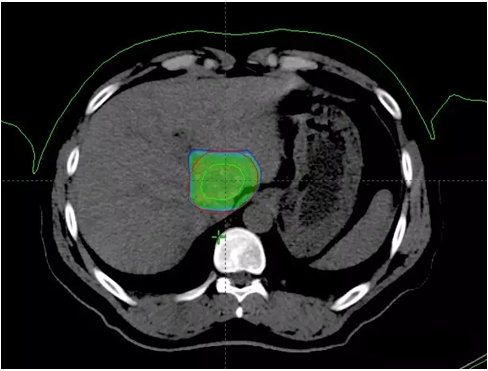

下圖分別為質(zhì)子治療的10% 50% 70% 95%的劑量分布情況,對(duì)正常的肝臟組織的有效保護(hù),充分顯示了質(zhì)子治療的劑量學(xué)優(yōu)勢(shì)。